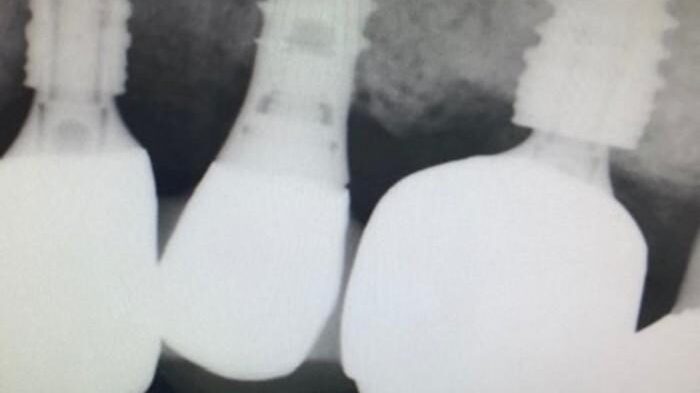

Nobel Active 3.5 fractured screw case: A Type II recovery using a concentric drilling technique – 0018

The patient presented on referral form Dr. S. for retrieval of a fractured abutment screw from a Noble Active 3.5 implant in the #29 site.